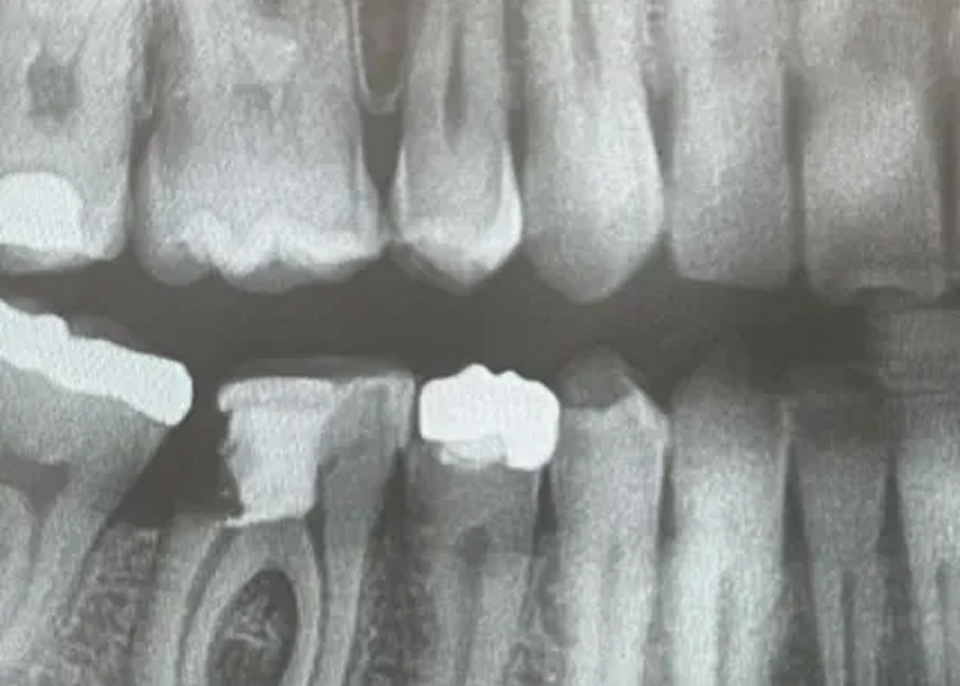

Direktimplantat efter tandutdragning – ett kliniskt exempel på när det lönar sig att vänta Direktimplantat efter tandutdragning är en behandlingsmetod som innebär att ett tandimplantat placeras direkt i alveolen efter att en tand tagits bort. När det används korrekt kan det ge mycket goda resultat med kortare behandlingstid och färre kirurgiska ingrepp. Men som med […]